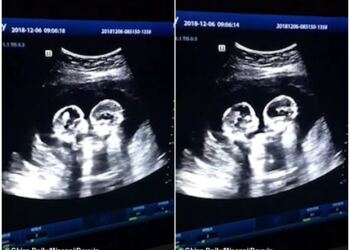

Οι νοσοκόμες επέμεναν ότι η μητέρα έπρεπε να ρίξει τα δίδυμά μωρά της, όταν όμως είδαν αυτό στο κινητό της ...

Όταν η 36χρονη Shellie Tucker ήταν 22 εβδομάδων έγκυος αντιμετώπισε μία έκπληξη. Εκείνη και ο άντρας της Greg θα αποκτούσαν ...